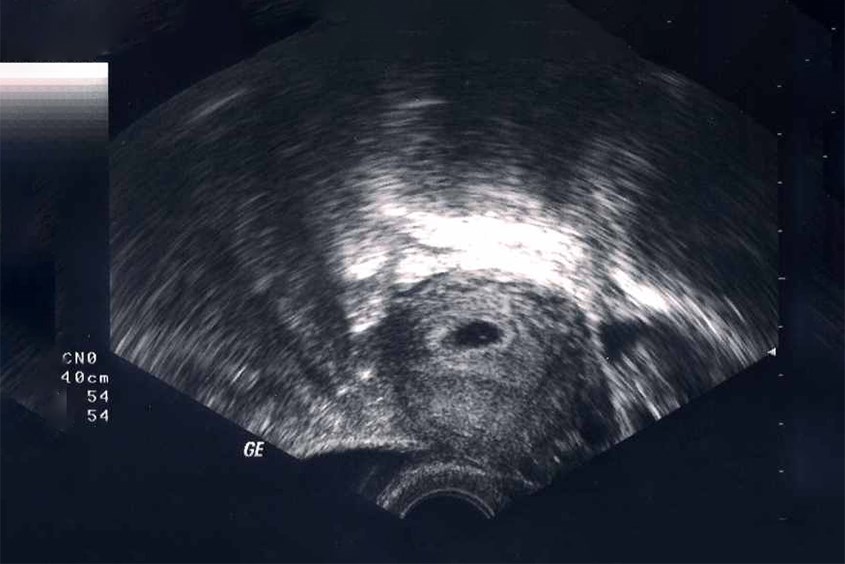

Mặc dù sự phát triển của thai nhi trong tuần đầu tiên chủ yếu diễn ra ở cấp độ tế bào và chưa có hình dạng rõ ràng, nhưng đây là giai đoạn đặt nền móng quan trọng cho một cuộc sống mới. Ngày dự sinh thường được tính là 40 tuần kể từ ngày đầu tiên của kỳ kinh cuối, tuy nhiên, thai kỳ có thể kéo dài hơn hoặc ngắn hơn một chút. Dù vậy, việc chuẩn bị kỹ lưỡng ngay từ tuần đầu tiên là điều cần thiết. Bởi lẽ, một nền tảng vững chắc sẽ giúp thai nhi phát triển khỏe mạnh và mẹ bầu có một thai kỳ khỏe mạnh, hạnh phúc.

Sự phát triển của thai nhi từng tuần